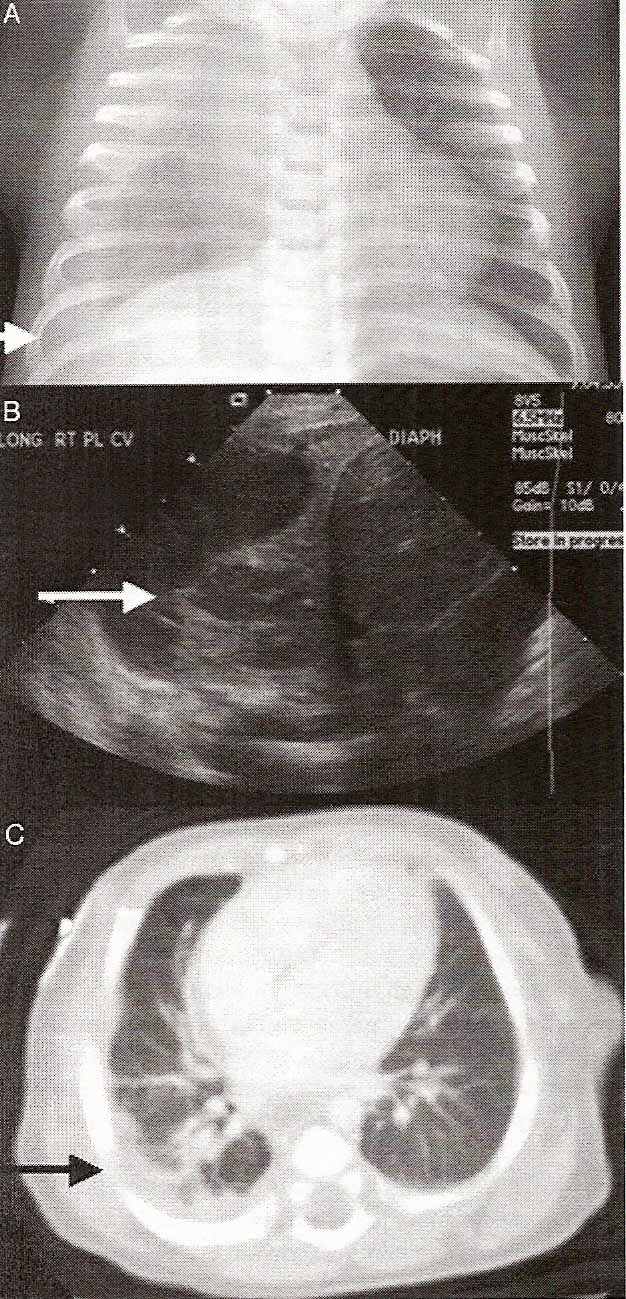

Chest radiograph and ultrasound showed a large complex right pleural effusion with septations and internal debris surrounding an area of lung consolidation resulting in mediastinal shift (Fig 1 A and B). Blood and cerebrospinal fluid (CSF) were obtained for culture. A thoracentesis revealed pleural fluid with Gram-positive cocci in clusters on Gram-stain. The infant was admitted negative. Rapid viral studies for respiratory syncytial virus and influenza as well as viral culture were also negative. Both pleural fluid cultures grew MRSA susceptible to clindamycin. After antibiotic susceptibilities were available, 14 total days of therapy was completed with clindamycin alone through day-of-age 42.

Figure 1: Imaging of CA MRSA right-sided pneumonia and empyema. Shown are a chest radiograph (A) and ultrasound (B) performed on admission and chest computed tomography (C) after video-assisted thoracoscopic surgery with chest tube placement. Arrows indicate loculated fluid.

The final chest tube was removed on day-of-age 31. Follow-up chest computed tomography on day-of-age 44 showed right-sided atelectasis and consolidation as well as fluid pockets in the right upper lobe suspicious for lung necrosis. The empyema was decreased in size (Fig 1C). After showing normal results from a nitroblue tetrazolium test, he was discharged on day-of-age 47.